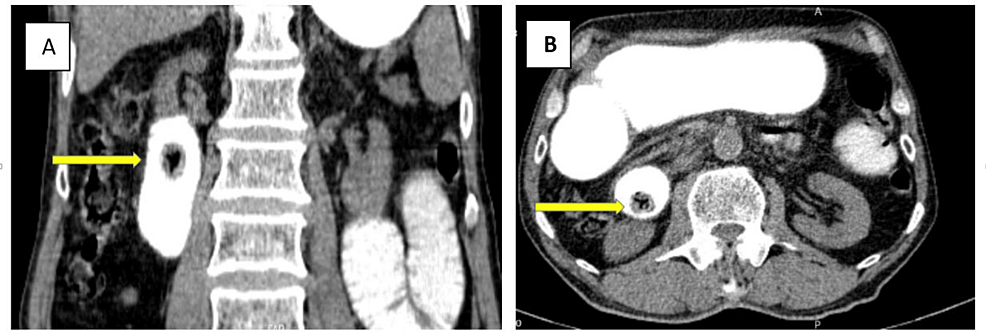

On the fifth postoperative day, after beginning an oral diet, mild colicky abdominal pain and bilious vomiting were revealed. A second abdominopelvic CT scan with oral contrast was performed, which demonstrated another duodenal ectopic non-obstructing gallbladder stone measuring 17 x 15 mm with a typical Mercedes-Benz sign in favor of recently migrated gall stone (Figure 3). Since the patient had no obstructive symptoms, conservative treatment and follow-up were opted for.

The classic presentation of gallstone ileus entails a “tumbling obstruction” in an elderly woman, indicating periodic subacute obstruction. Episodic and transient gallstone impaction results in nonspecific, generalized abdominal pain and vomiting. In our patient, a smaller migrated gallstone was also found, which, under our careful observation, resembled a “tumbling obstruction” and spontaneously resolved. The minimum size of the ectopic stone that leads to the development of obstruction is 2.5 cm in diameter. In the study by Clavien et al., the size of obstructing gallstone ranged from 2 to 5 cm [9]. Multiple gallstones have been reported in 3-40% of cases, which were found to be responsible for recurrent gallstone ileus episodes [11].

As mentioned before, our patient underwent enterolithotomy alone, and the main reasons for preferring this approach were severe inflammatory changes and many adhesions around the gallbladder, which increased the risk of iatrogenic injuries. Also, the patient’s advanced age, presence of comorbidities, and poor compliance played a role in this decision. In the case of the second ectopic stone, which was detected in the follow-up CT scan, we preferred conservative treatment over re-enterolithotomy due to the stone size and absence of clear obstruction signs, and it passed through the GI tract, fortunately. CT scan had a significant role in our decision-making, as it enabled us to estimate the size and location of the stone and choose the non-surgical option for treatment.